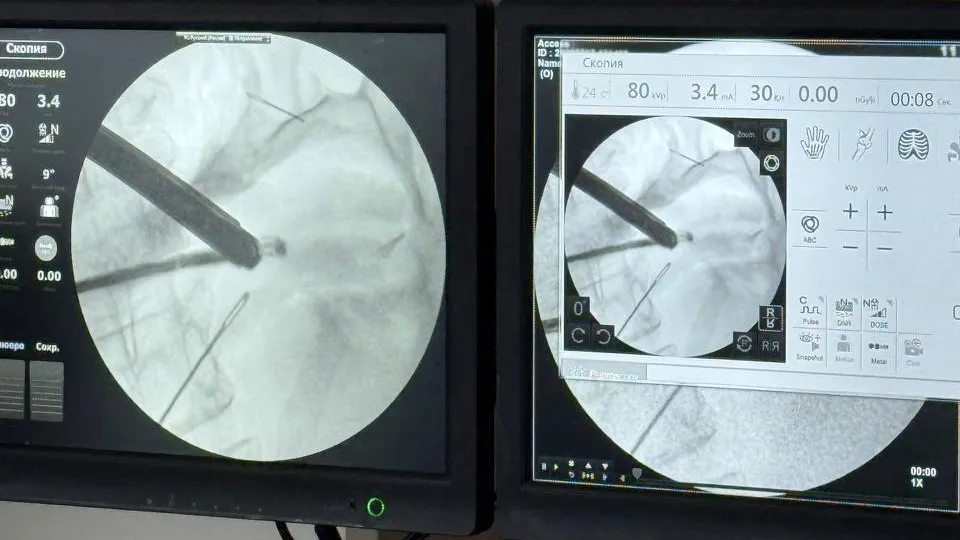

В Красногорскую больницу поступила 59-летняя пациентка с жалобами на боль в животе. Врачи провели обследование и обнаружили в брюшной полости четыре швейные иглы.

Женщина рассказала, что около месяца назад проглотила посторонние предметы, которые за это время частично обросли тканями.

«Изначально мы планировали лапароскопию — операцию через небольшие проколы, но из-за открывшегося кровотечения пришлось перейти на лапаротомию — рассечение передней брюшной стенки. В результате мы смогли успешно удалить все четыре иглы», — пояснил заведующий первым хирургическим отделением Николай Мурашов.

Острые предметы проникли сквозь стенки желудка, а один из них даже достиг поджелудочной железы. К счастью, специалисты смогли сохранить орган.